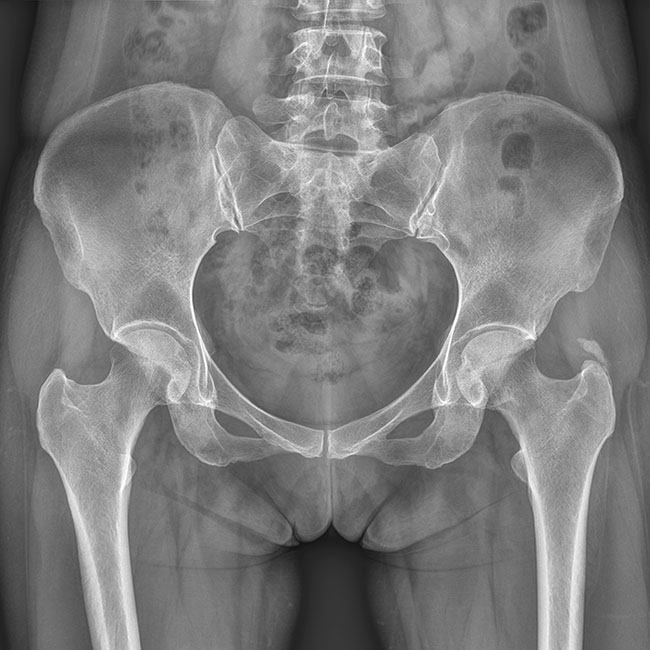

全自動狹縫拼接功能

垂直投影無畸變,反映真實骨骼結構

一鍵快速全脊柱/全下肢全景成像支持臥位和站立位檢查,成像劑量低

臨床樣本